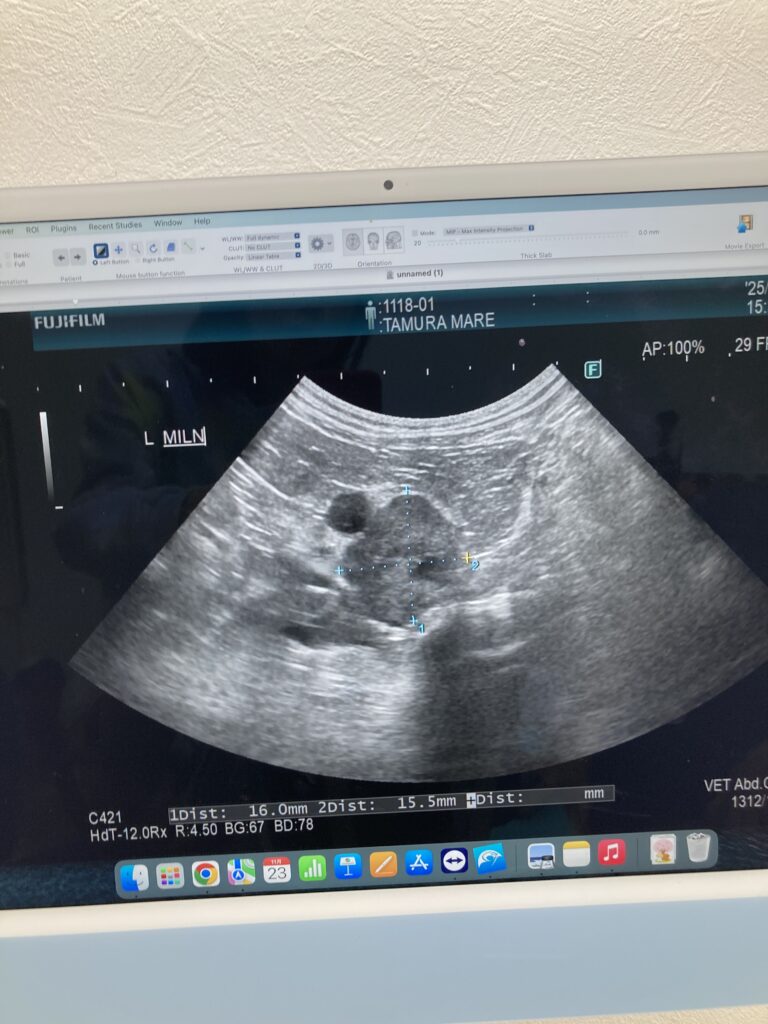

• 内容:手術前検査(リンパ節の超音波と細胞診検査)

手術前に転移がないか確認するため、

リンパ節の超音波検査をしました。

結果、リンパ節転移と思われるものが2ヶ所に…

(最低2ヶ所とのこと)